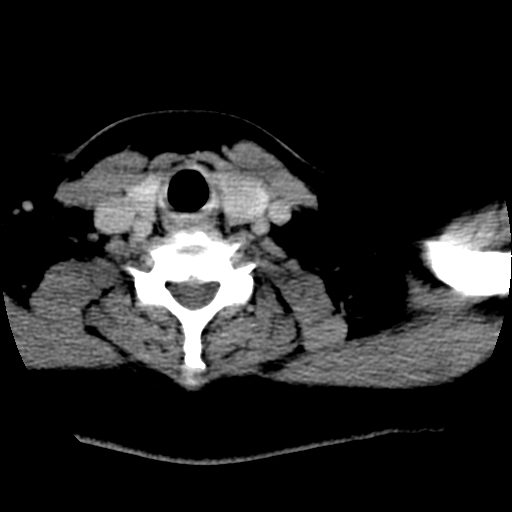

标题: CT25491:女,55岁,发现左侧甲状腺肿块一个月。 [打印本页]

女,55岁,发现左侧甲状腺肿块一个月,彩超示:甲状腺多发结节伴左叶结节液化。

左右叶都有,峡部也受累,有钙化,考虑结甲可能性大。

考虑右叶结节性甲状腺肿,伴左叶钙化。主要(1)密度均匀,边境清。(2)病灶与血管界限清。